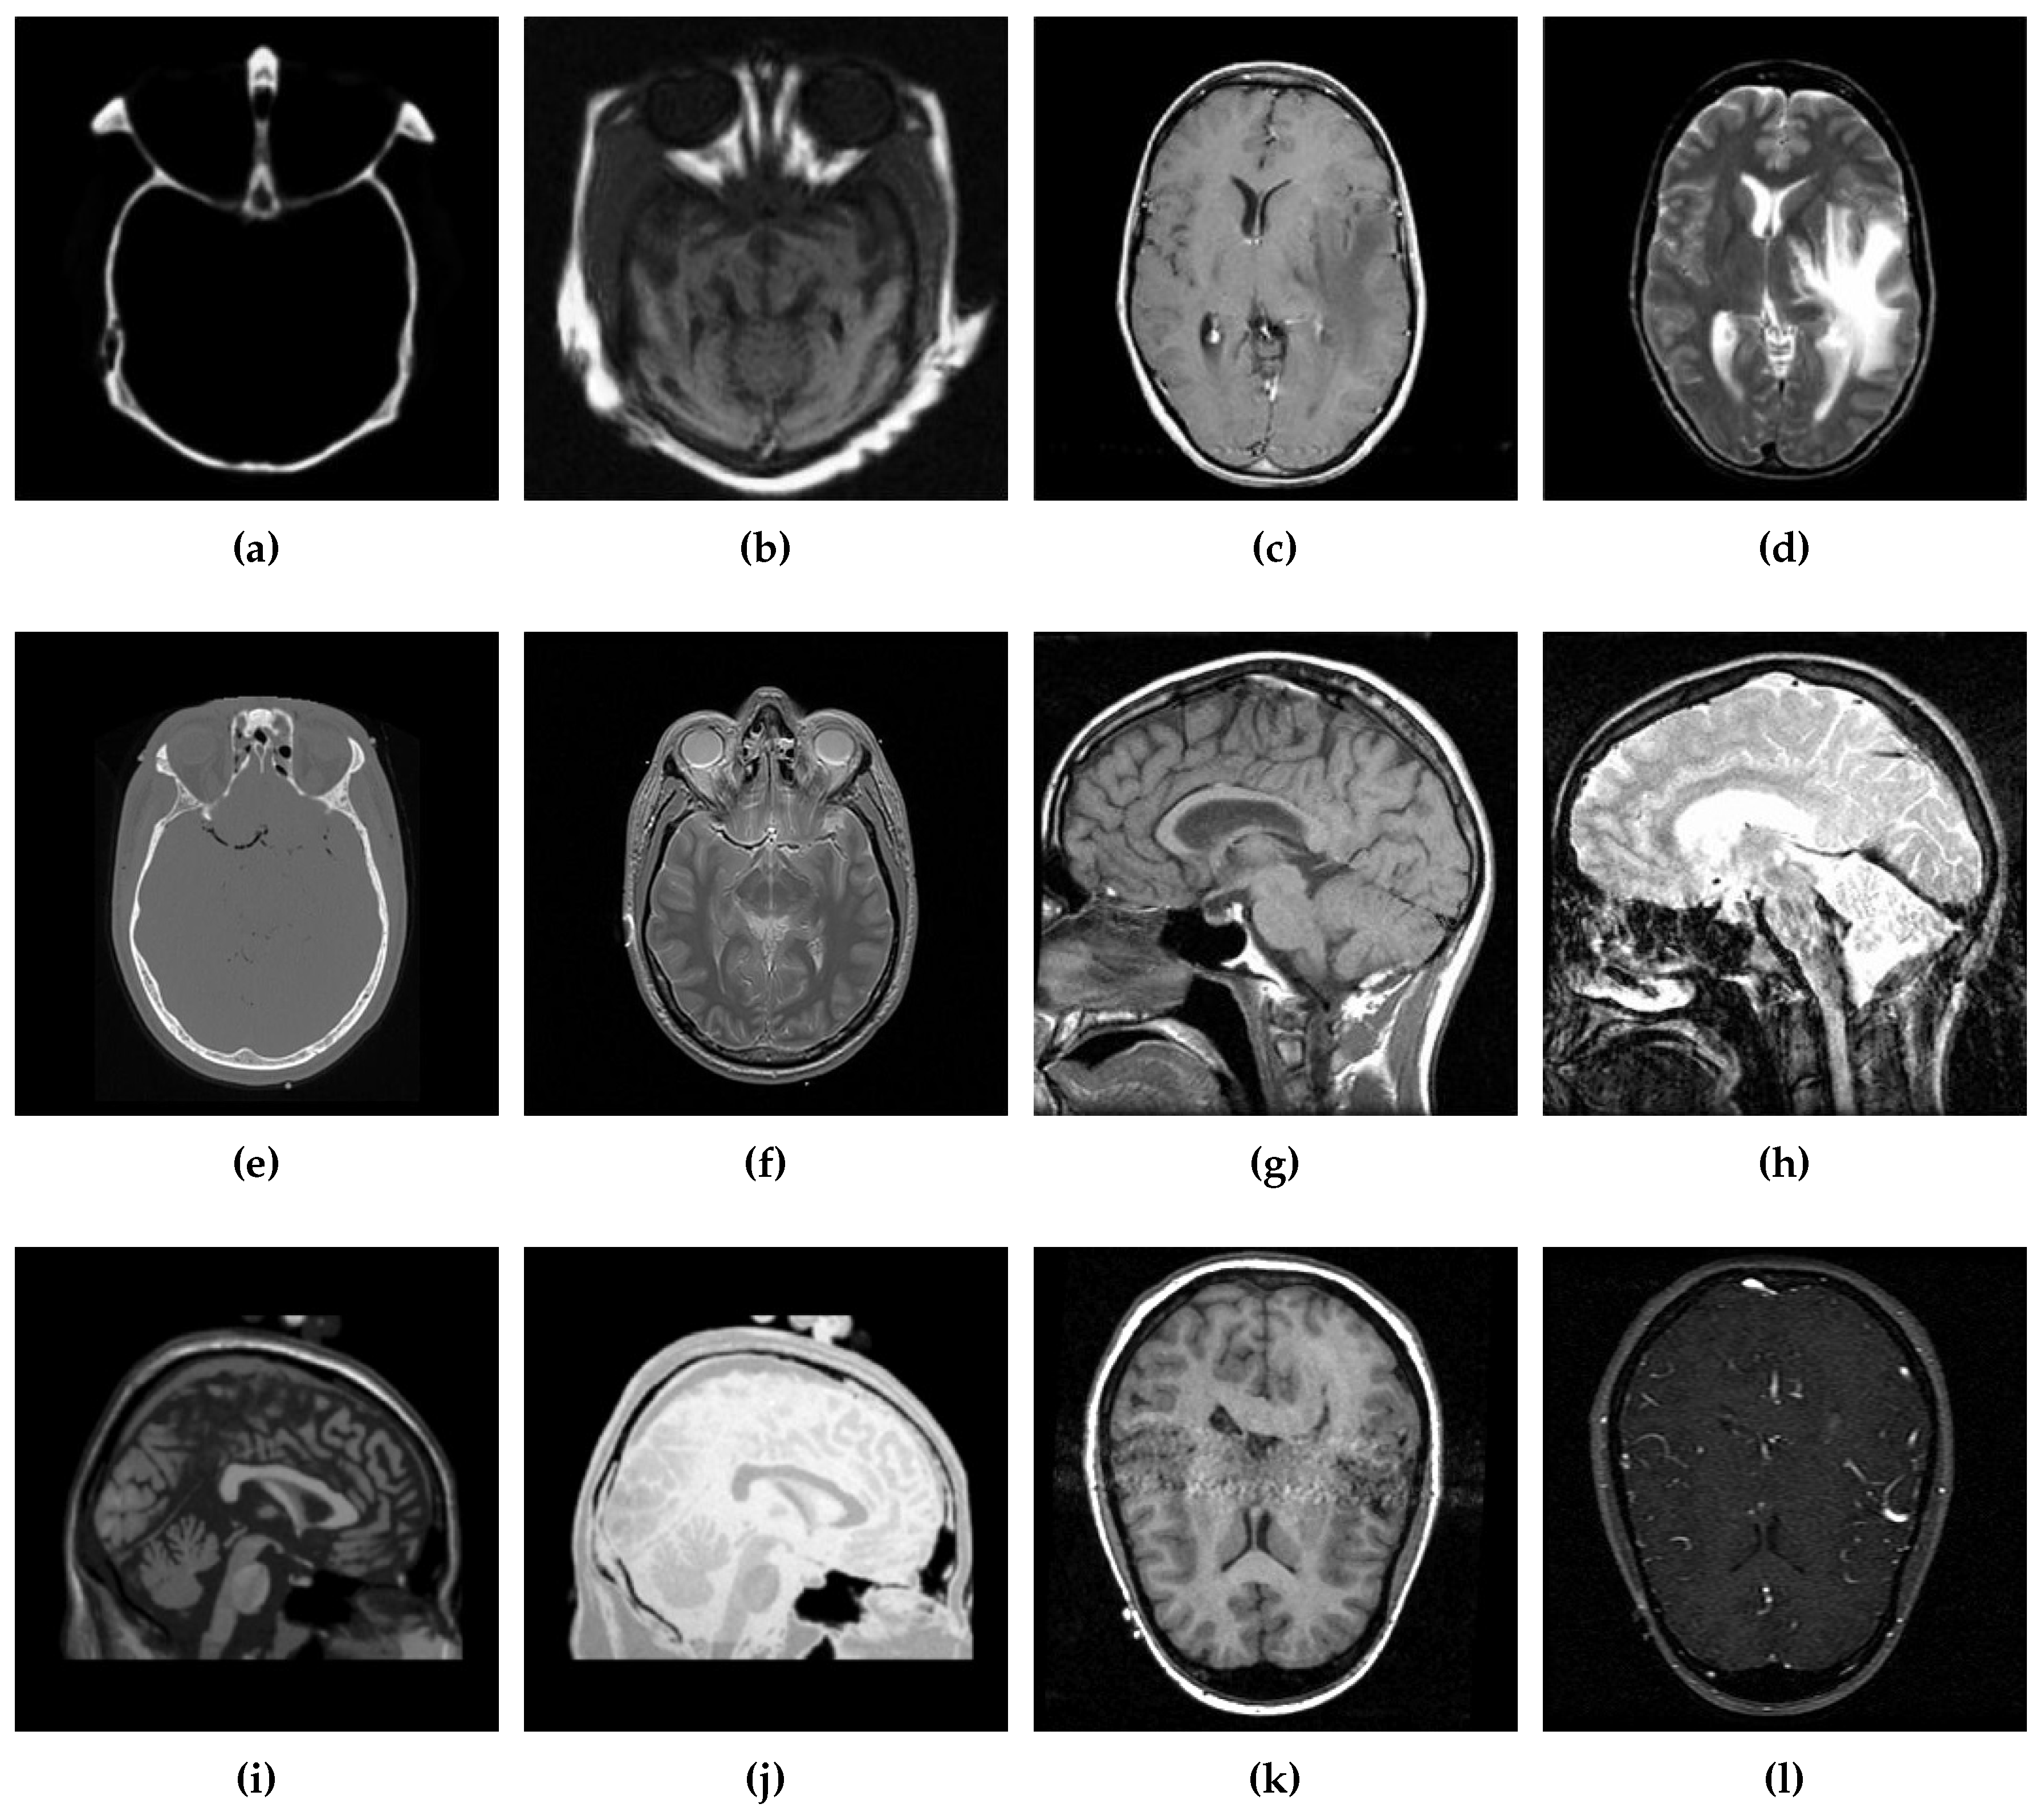

Six different datasets of multimodal images, referred as Data-1 through Data-6, are used in the simulations. Figure 4 depicts sample images from the aforementioned datasets. The fusion results, generated by our proposed CSID algorithm and the aforementioned eminent fusion algorithms, are shown in Figure 5, Figure 6, Figure 7, Figure 8, Figure 9 and Figure 10. Each result presented is averaged over 20 replicated simulation runs by keeping all the parameters fixed and changing the random seed values. The following subsections demonstrate and discuss the obtained results.

Figure 4. Sample source images from the given datasets (Data-1 through Data-6), where (a,b) ∈ Data-1, (c,d) ∈ Data-2, (e,f) ∈ Data-3, (g,h) ∈ Data-4, (i,j) ∈ Data-5, and (k,l) ∈ Data-6.

Diagnostics 10 00904 g004